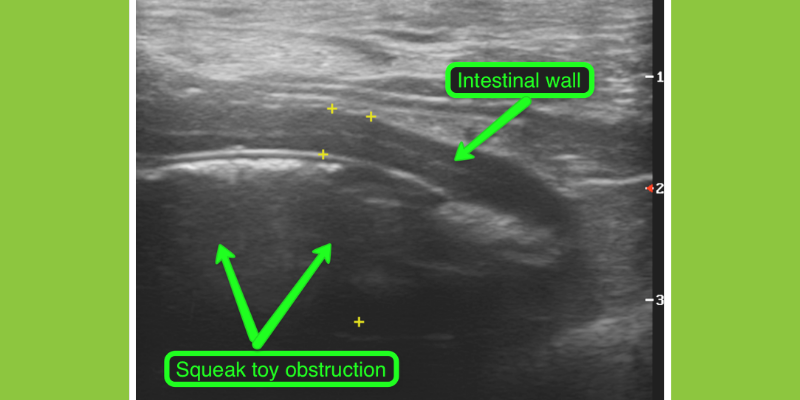

Ultrasound image of the intestines in a cat. The intestinal wall is thickened with abnormal layer distribution with the appearance highly typical of inflammatory bowel disease or occasionally a cancer called small cell lymphoma. These layer changes are not visible on x-rays.

Ultrasound image of the intestines in a vomiting dog. The smooth oval structure is a squeaker toy that is causing obstruction of the intestines. This foreign body was not visible on x-rays, but the intestinal dilation was concerning and warranted further investigation.